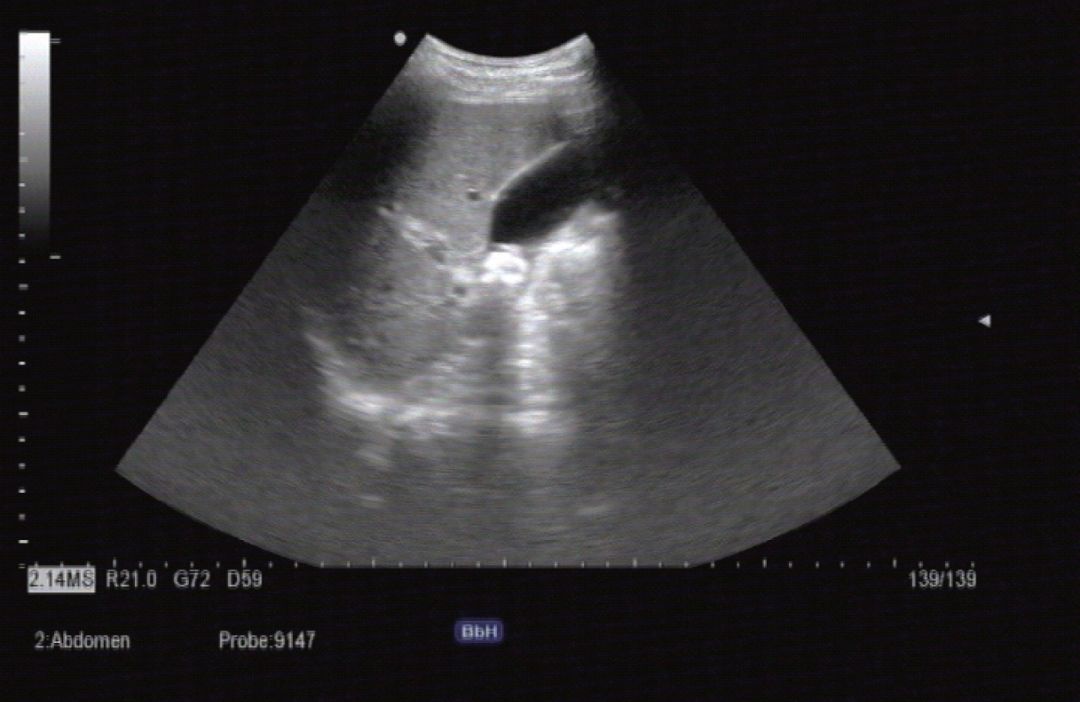

(2) 病例

1) 病史:患者男,50岁,自觉右上腹不适就诊。

2) 超声描述: 胆囊腔内可见强回声光团后伴声影改变体位后可见此强回声光团移动。